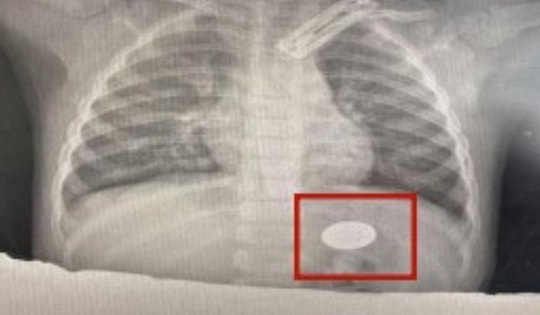

Vi khuẩn kháng thuốc tấn công thùy phổi bé trai